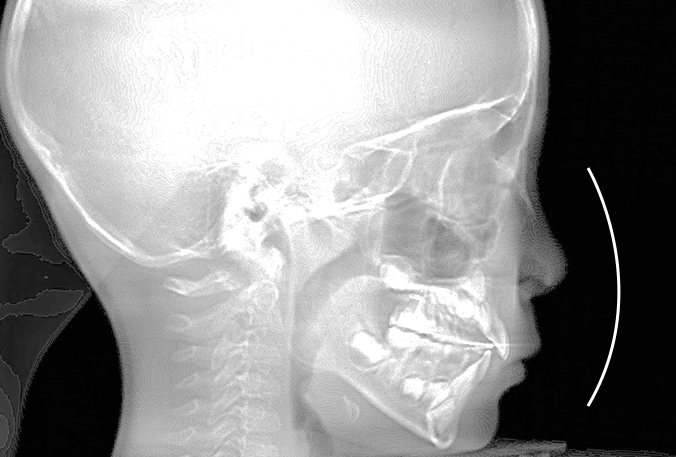

20代女性の患者さま。

八重歯の見た目が気になってご来院されましたが、実は顎の痛みや開口障害など、顎関節症の症状もありました。

そのため、かみ合わせと顎関節症の治療を同時に行ったにもかかわらず、2年間で治療が終了。

かみ合わせが整い咬筋の過緊張も改善しました。咬筋の肥大も治ってフェイスラインがすっきりしました。

最終的には美しい歯並びと、安定した痛みのないかみ合わせが実現しました。

八重歯が気になる

叢生、顎関節症、開口障害

20代女性

矯正治療2年

24回

唇側矯正

矯正:1,161,600円+毎月調整量:6,050円

しっかり前歯を下げるために、インプラントアンカーを使用してコントロールしました。

かみ合わせが整うと咬筋の過緊張が改善。

過緊張による筋肉肥大も改善しフェイスラインもすっきりしました。